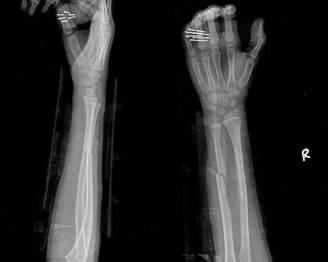

摘要:最新尺橈骨融合方法展現(xiàn)骨頭間的奇妙和諧與友情力量。通過先進(jìn)的醫(yī)療技術(shù),尺骨和橈骨之間的融合得到顯著改善。這種方法不僅提高了治療效果,還展現(xiàn)了人體骨骼之間的和諧關(guān)系。憑借友情和信念的力量,醫(yī)學(xué)界不斷突破,為患者帶來福音。

在醫(yī)生的介紹下,他們了解到了一種最新的尺橈骨融合治療方法——通過微創(chuàng)手術(shù)進(jìn)行骨骼融合的新技術(shù),這種方法不僅減少了手術(shù)風(fēng)險,還能更快地恢復(fù)活動能力,雖然小明感到害怕,但他的朋友們一直陪伴在他身邊,給予他勇氣和力量。